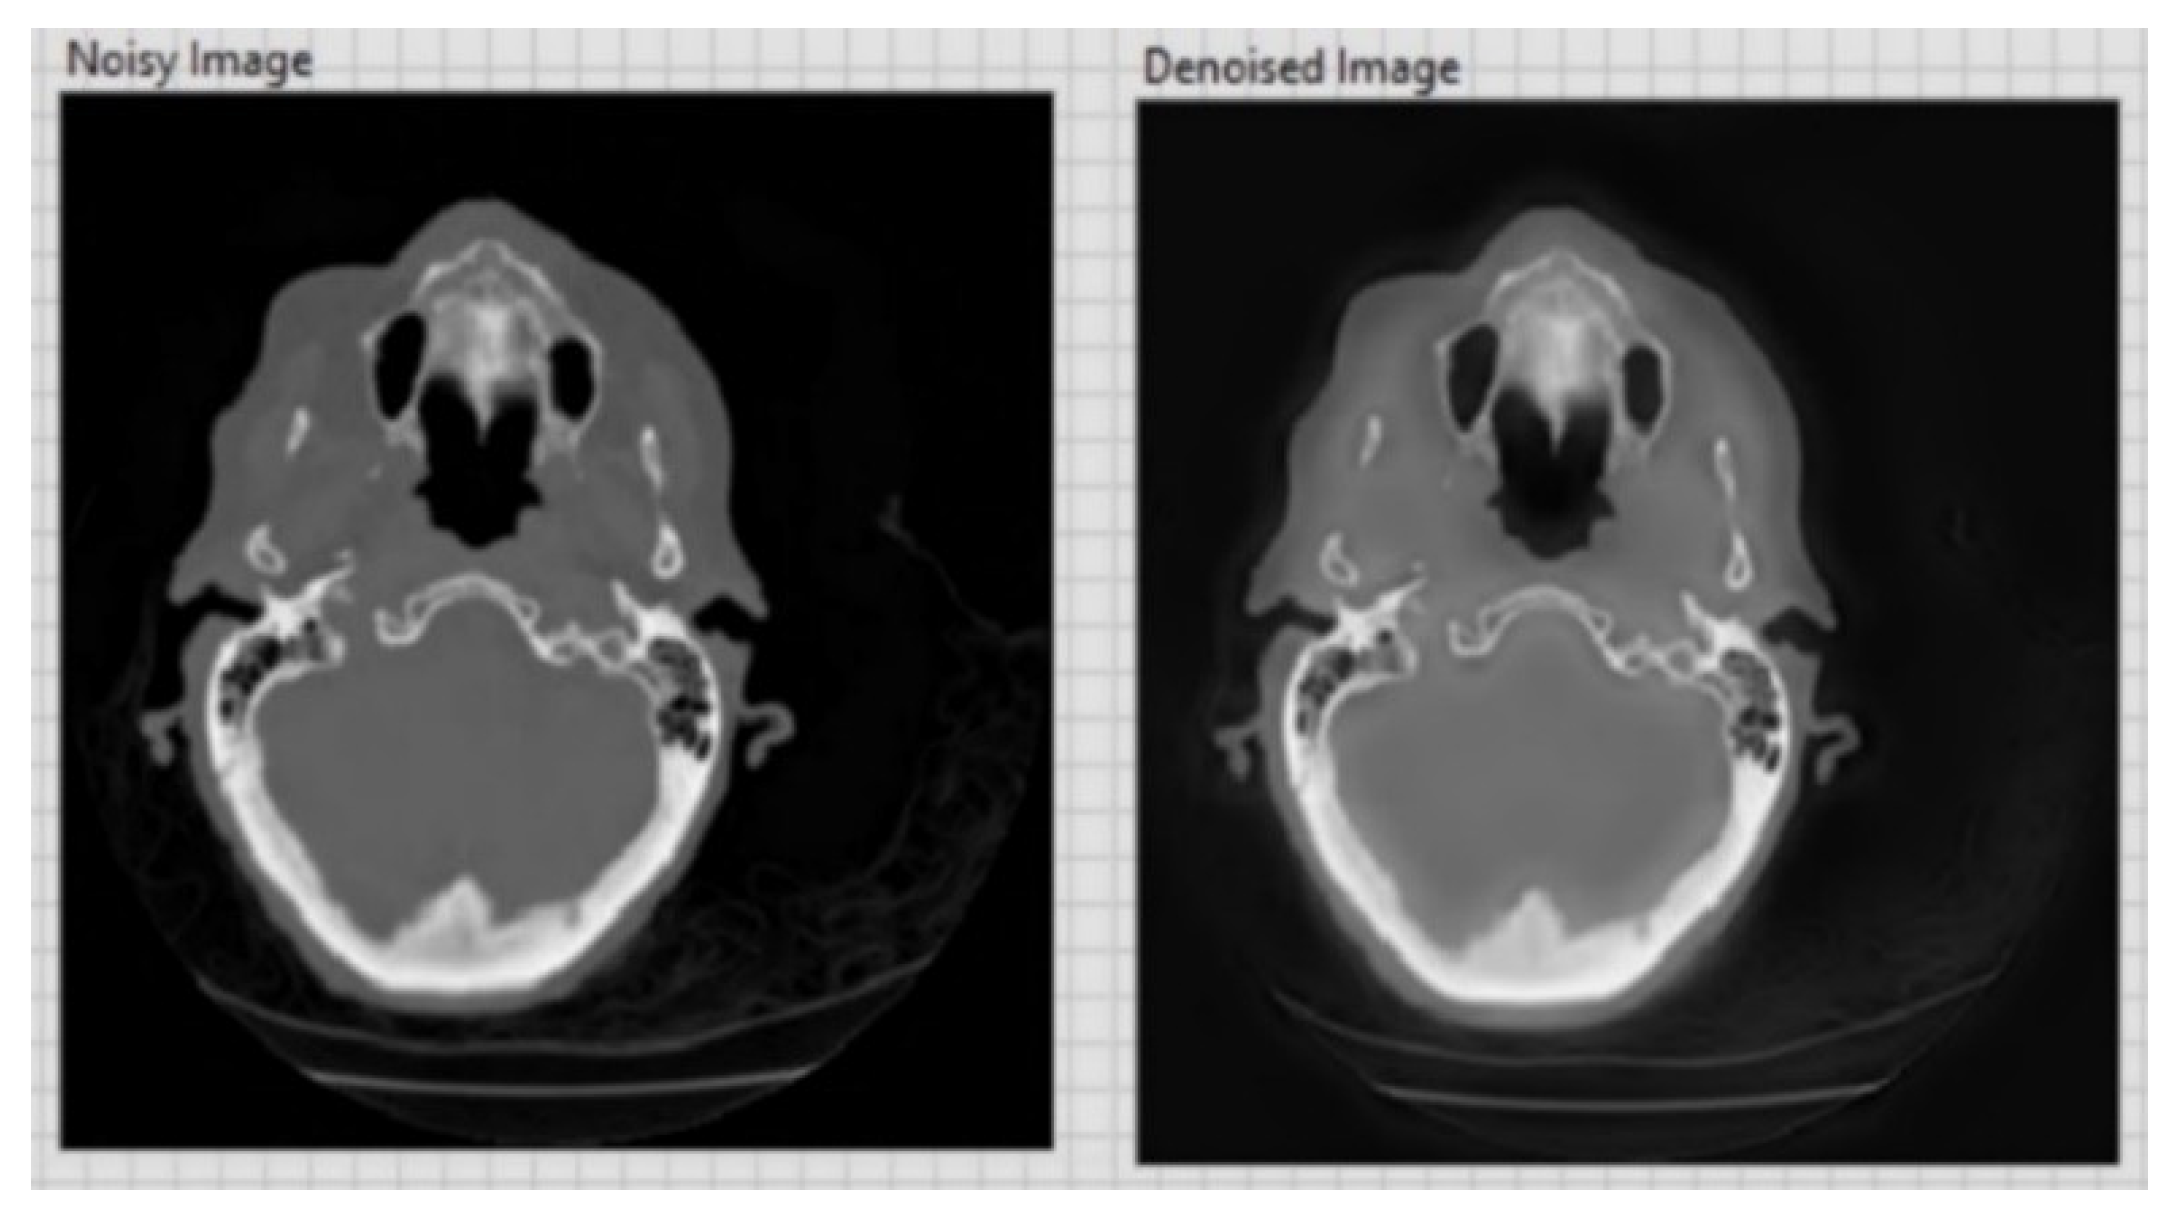

- Improving image quality by selectively eliminating disturbing information, such as noise, and eliminating other defects caused by the acquisition device by using adaptive filters.

| CT image (Figure 6) 256 × 256 | 26.01 | 0.05 |

| CT image (Figure 7) 256 × 256 | 20.15 | 0.1 |

| CT image (Figure 8) 256 × 256 | 20.13 | 0.1 |

| CT image (Figure 9) 256 × 256 | 26.09 | 0.05 |

| CT image (Figure 10) 256 × 256 | 20.18 | 0.1 |

| CT image (Figure 11) 256 × 256 | 26.15 | 0.05 |